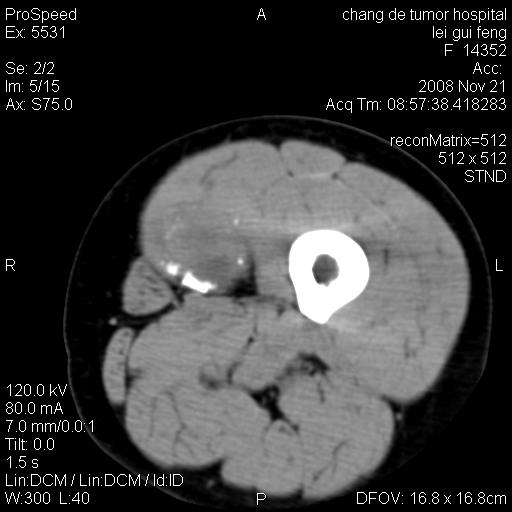

标题: CT16807:女 41 无不适 [打印本页]

标题: CT16807:女 41 无不适

考虑皮样囊肿可能性大

血管瘤可能

血管瘤

血管瘤可能性大!

黏液瘤或表皮杨囊肿

不排除横纹肌肉瘤可能。

血管瘤可能性大或畸胎瘤

考虑脂肪肉瘤

考虑血管瘤可能性大;不排除肉瘤可能。建议行活检。

脂肪肉瘤?

双是软组织肿瘤,病灶内多发钙化,另可见多量脂肪密度影,考虑畸胎瘤,血管瘤,不除外其他